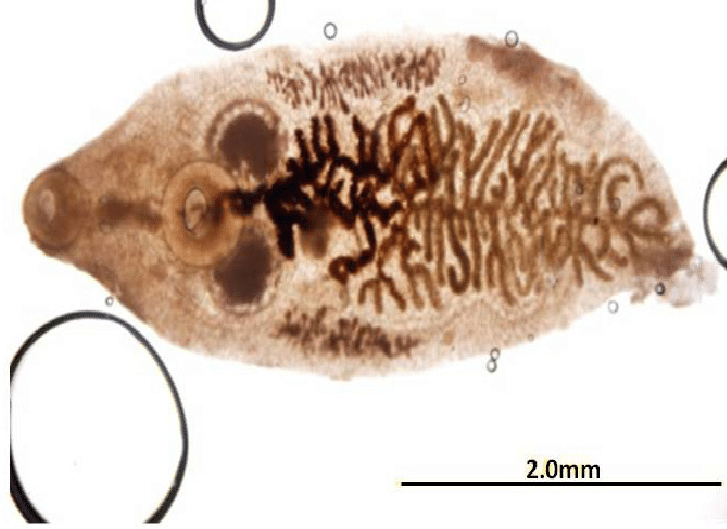

E o Platynosomum fastosum fica alojado no duto biliar do gatinho.